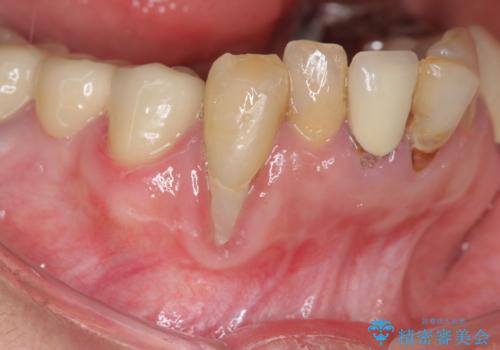

[ 重度歯周病 ] インプラント・義歯による咬合再構築

![[ 重度歯周病 ] インプラント・義歯による咬合再構築の症例 治療前](https://seimitsushinbi.jp/wp/wp-content/uploads/2021/07/0a652e75d5f31b51f66fbb3c46093249-500x350.jpg?v=1626759388)

![[ 重度歯周病 ] インプラント・義歯による咬合再構築の症例 治療後](https://seimitsushinbi.jp/wp/wp-content/uploads/2021/07/4c6838854beaf5801dbc7fde26492d6c-500x350.jpg?v=1626759531)